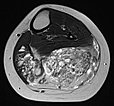

Axial T2-weighted MRI of the left lower leg shows multiple dilated, dysplastic veins in a venous malformation throughout the superficial flexor muscles. Slow flow causes stasis of the blood within the malformation with the formation of fluid-fluid levels. Almost the entire muscle consists of malformation and fatty tissue. Also visible is a large thrombus in a dilated, dysplastic vein.

In coronal, non-enhanced T1-weighted control MRI, the vascular component of the lesion is less conspicuous. However, clearly additional soft tissue remains that is pathologic (“salt-and-pepper pattern”). This tissue consists in part of hyperintense adipose tissue and in part of hypointense connective tissue. This is the typical MRI appearance of a fibro-adipose vascular anomaly (FAVA).

The vascular channels are largely occluded on axial control MRI in T2-weighted images. However, after successful occlusion of the vascular channels, a black-and-white “salt-and-pepper” pattern typical of FAVA remains. This consists of adipose tissue (hyperintense) and connective tissue (hypointense).